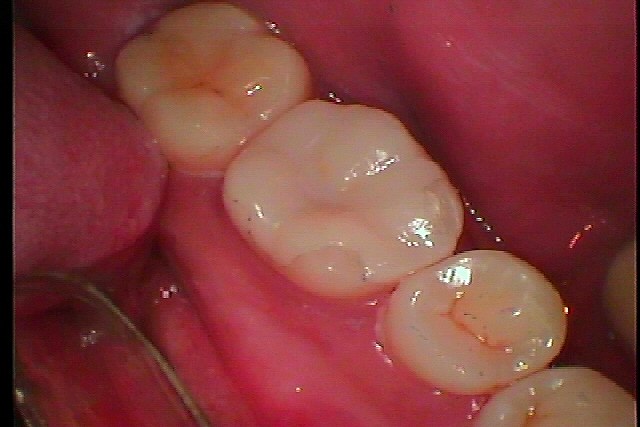

左下6番のセレックセラミック治療にになります 虫歯が大きく神経まで近い歯になります|お知らせ |広島市安佐南区の歯科医院 左下6番のセレックセラミック治療にになります 虫歯が大きく神経まで近い歯になります トップ お知らせ・ブログ お知らせ 左下6番のセレックセラミック治療にになります 虫歯が大きく神経まで近い歯になります 左下6番のセレックセラミック治療にになります 虫歯が大きく神経まで近い歯になります こんな銀歯が入っていました 銀歯との隙間に穴が開いています かなり色も悪く黒いです 真っ黒になっていました 大きな虫歯が存在しています 虫歯を神経に気お付けながら除去していきました CRにて覆罩していきます セレックセラミックにて修復していきます きれいに仕上がりました 他もきれいにしたいとのこと Web診療予約 初めての方へ 選ばれ続ける理由 院内設備について 歯が痛いしみる一般歯科 歯がぐらぐらする歯周病 健康な歯を保ちたい予防歯科 子供の虫歯予防をしたい小児歯科 銀歯をセラミックに審美歯科 白い歯を目指しませんか?ホワイトニング 矯正専門医がいるので安心矯正歯科 抜けた歯を補いたいインプラント・入れ歯 医院案内 スタッフ紹介 メリィハウス歯科クリニックオフィシャルホームページ ラベンダー歯科クリニックオフィシャルホームページ お知らせ・ブログ ホーム 診療科目 一般歯科 歯周病治療 予防治療 小児歯科 審美治療 ホワイトニング 矯正歯科 入れ歯・インプラント マウスピース矯正 初めての方へ 院長・スタッフ 設備紹介 医院案内・アクセス メニューを閉じる